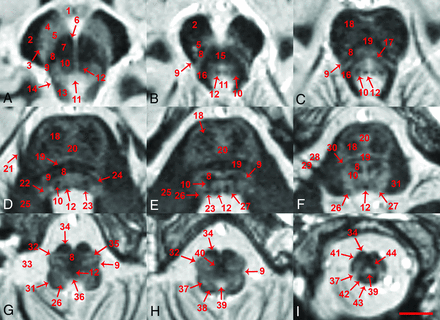

The FGATIR sequence provided novel MR imaging–derived contrast throughout the in vivo brain stem and allowed the direct identification of many small functionally important structures. Structure identification by 2 neuroradiologists was facilitated by 3-plane cross-referencing. Selected serial axial images illustrate contrast resolution of internal brain stem anatomy at canonical levels (Fig 1). Selected coronal and sagittal images also reveal excellent contrast resolution of internal brain stem anatomy (Figs 2 and 3, respectively). Such longitudinal images demonstrate the superior-inferior course of several brain stem pathways and the potential for the 0.8-mm isotropic FGATIR to enhance our understanding of the 3D organization of the brain stem. Videos of axial, coronal, and sagittal images through the brain stem are provided to interested readers on-line (On-line Videos 1–3).

Superior-to-inferior axial in vivo MR images parallel to the intercommissural plane for the brain stem (number denotes the position below the plane), including the superior midbrain (A, 8.8 mm), inferior midbrain (B, 15.2 mm), midbrain-pons junction (C, 18.4 mm), superior midpons (D, 25.5 mm), inferior midpons (E, 29.5 mm), inferior pons (F, 35.9 mm), superior or “open” medulla (G, 43.1 mm), closed medulla at the sensory decussation (H, 47.1 mm) and motor decussation (I, 55.1 mm). A 26-year-old healthy control female subject, 0.8-mm isotropic resolution, 9 individual datasets coregistered and averaged, 2 imaging sessions with ∼2-hour 15-minute total scan time (scale bar = 5 mm). Please see the Table and Results section for explanation of labeled structures.

Within the brain stem, the signal intensity or brightness of a specific structure appeared inversely correlated with the intensity of myelin staining in postmortem histology atlases.48⇓-50 Blood in the vertebral arteries and dural venous sinuses appeared the brightest. The next most hyperintense structures were CSF and adjacent gray matter such as the periaqueductal gray and area postrema, the latter a circumventricular organ with an altered extracellular matrix and vascular structure.51,52 The third most hyperintense structures were more central gray matter within the brain stem such as the substantia nigra and pontine nuclei. Structures with intermediate hyperintensity were less compact or less densely myelinated structures like the inferior colliculi, central tegmental tract, and corticonigral pathways. Dark structures were classic myelinated brain stem pathways such as the medial longitudinal fasciculus, medial lemniscus, and pontocerebellar fibers. The darkest structures were densely myelinated pathways, including the medullary pyramids, superior/middle cerebellar peduncles, and larger cranial nerves. Cortical bone in the central skull base and the tectorial membrane also appeared very dark. Of note, the signal intensity (and shape) of the corticospinal tract varied along its course, appearing dark within the cerebral peduncles and medullary pyramids, but more diffuse and relatively brighter within the basis pontis. This appearance may represent interdigitation of pontine nuclei and pontocerebellar projections between white matter fascicles of the corticospinal tract.48⇓-50,53

Labeling in the figures emphasizes unambiguous structures that can be identified well on the images. Most of these labeled structures are well-known to clinicians familiar with brain stem anatomy (eg, the medial longitudinal fasciculus). Directly labeled visible structures also can be used to generate more exact indirect localization for other bordering internal brain stem structures. Figure 4 provides a highly detailed example of this approach for the inferior midbrain where the likely positions of multiple additional structures can be estimated relative to the borders and anatomic spaces formed between the medial longitudinal fasciculus, medial lemniscus, and decussation of the superior cerebellar peduncles. Annotation at this level of detail with descriptions of functional relevance is possible throughout the brain stem, but is beyond the scope of this initial report. Other selected examples of indirect localization that may be of general interest include the oculomotor complex (bright region posteromedial to the central tegmental tract in Fig 1A), pedunculopontine nucleus (bright region medial to the medial lemniscus and lateral to the decussation of the superior cerebellar peduncles, in Fig 1B), locus coeruleus (bright region posterior to the central tegmental tract and medial to the superior cerebellar peduncle in Fig 1C), and facial nucleus (bright region posterolateral to the central tegmental tract and medial to the cerebellar peduncles in Fig 1F). An inferior notch along the medial aspect of the left middle cerebellar peduncle with gray matter signal intensity in Fig 2D is the cochlear nucleus.

There also are subtle features in the images that are difficult to assign with certainty (and sometimes only visualized on 1 side) that likely correspond to specific structures better resolved with postmortem MR microscopy53 and histology atlases.48⇓–50 Limited visualization may be from partial volume effects due to the small size of the structures relative to 0.8-mm isotropic voxels and/or less contrast relative to surrounding nervous tissue. On the right side of Fig 1B, there is an arc-like medially concave dark structure oriented anterior-posterior, consistent with the expected location of the left oculomotor nerve. In Fig 1C, -D, the tectospinal tract appears as a faint dark dotlike structure anterior to the medial lemniscus, particularly on the left side. In Fig 1E, the left tectospinal tract is more obvious, but there is marked asymmetry compared with the subject’s right side. Also, in Fig 1E, the indistinct anterior margin of the medial lemniscus may represent the anteromedial continuation of the trapezoid body. In Fig 2D, an intermediate signal intensity line oriented inferomedial to superolateral, dividing the area postrema (on the right side of the image), may be the sulcus limitans. Some structures also are better recognized when the imaging plane is transverse to the structure. For example, the facial nerve in the lateral midpons is difficult to appreciate in the axial plane (Fig 1F), but better resolved in the coronal plane (Fig 2D).

The FGATIR images did not discriminate all brain stem structures well. It was not possible to distinguish the corticospinal tract from other white matter in the cerebral peduncle (Fig 1A). Boundaries of the medial lemniscus, tectospinal tract, and medial longitudinal fasciculus, which are adjacent to one another in an anterior-posterior orientation within the medulla, remain indistinct (Fig 1G). The inverse relationship of MR imaging signal intensity to white matter content described above also was not entirely consistent. For example, the red nucleus appeared isointense to enveloping cerebellorubral and cerebellothalamic fibers on MR imaging, but these structures are more distinct with classic white matter staining on histology.48,49